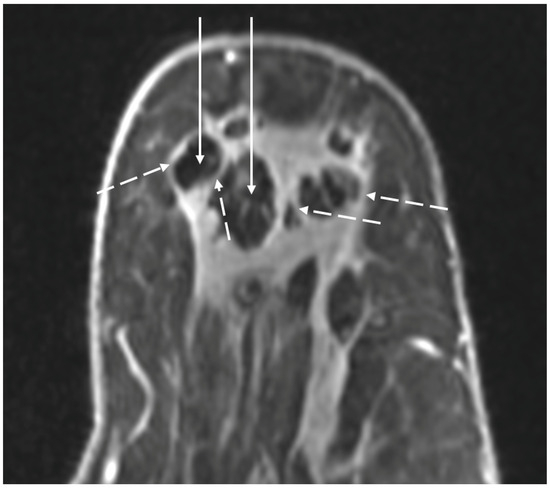

Digital Mammography. Breast cancer staging should include bilateral digital diagnostic mammograms (preferably 3D mammograms or tomosynthesis) to evaluate the extent of disease. Although cryoablation is generally performed under ultrasound or CT-scan guidance, high-quality mammography might reveal additional areas of cancer in the same region of the breast (multifocal cancer) or in a different region of the breast (multicentric cancer) that might impact patient selection or alter the cryoablation treatment plan. Multicentric and multifocal breast cancer is generally regarded as a contraindication to cryoablation. Pre-treatment assessment of the mammograms should seek the detection of spiculations (radial tumor extensions) and/or microcalcifications that might reach beyond the main tumor mass and require incorporation in the cryoablation treatment zone (Figure 1). Since mammography is the only imaging study that reliably shows microcalcifications, mammography plays a particularly important role in determining disease extent when suspicious microcalcifications are part of the disease process. Consequently, patients who are generally opposed to obtaining screening mammograms should be encouraged to have at least one set of pre-treatment diagnostic mammograms to exclude the presence of suspicious microcalcifications that could impact patient selection and/or treatment planning.

Figure 1.

Mammogram showing density corresponding to a palpable mass (see dashed lines) as well as suspicious microcalcifications (arrows) and inset image showing magnified view of white punctate calcifications extending beyond the palpable mass.